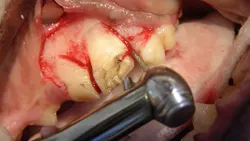

Step 4

The buccal alveolar bone is removed using a round ball bur (#2, surgical length, friction grip) in a water-cooled, high-speed handpiece. The amount removed will depend on the experience and skill of the operator, but removing the alveolar bone to expose 25% to 50% of the buccal root surface should suffice. The removal of alveolar bone is guided by palpation and visualization of the alveolar juga of each root.